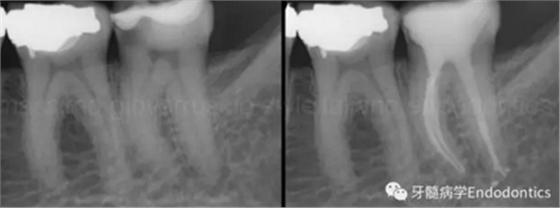

圖1.探查冠方2/3可以獲得有關(guān)根管系統(tǒng)解剖形態(tài)的相關(guān)信息,獲得根管彎曲和多重彎曲程度,或者是否存在根管彎曲的一些重要反饋。醫(yī)生需要重視五種可能遇到的根管解剖類型(包括融合、彎曲、多重彎曲、分歧、分支)。

當(dāng)建立直線通路、找到所有的根管口后,重心應(yīng)轉(zhuǎn)移到根管預(yù)備上。若牙髓存在活力且持續(xù)滲血,應(yīng)使髓室內(nèi)充滿粘性螯合劑。在牙髓已壞死的情況下,應(yīng)使用加熱的5.25%次氯酸鈉溶液沖洗并徹底充滿髓室。探查前,根據(jù)術(shù)前X線片測量并預(yù)彎小的不銹鋼銼,以順應(yīng)預(yù)估的根管長度及彎曲度。使用0.02錐度的10號不銹鋼手用K銼探查根管冠方2/3。